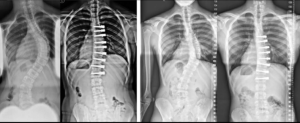

Skolyoz sadece ameliyat ile tedavi edilebilir: YANLIŞ

DOĞRUSU: Ortopedi ve Travmatoloji Uzmanı Prof. Dr. Mehmet Tezer “Skolyoz hastalığının ameliyat devresinden önce kesinlikle egzersiz ve/veya korse tedavisi ile izlenmesi ve ameliyatsız tedavi edilebilmesi söz konusudur. En önemli konu; hastalığın erken evrelerde daha küçük derecelerde yakalanabilmesidir. Bu sayede önemli sayıda hasta ameliyatsız sağlığına kavuşabilmektedir” diyor.

Skolyozda cerrahi tedavi 18-20 yaşına kadar yapılamaz: YANLIŞ

DOĞRUSU: Skolyoz ameliyatı ihtiyaç olduğu taktirde yapılabilmektedir. Doğuştan olan skolyozlarda genellikle 5 yaşın altında bile ameliyatlar gerçekleştirilmektedir. Ancak skolyozun derece ve denge hesaplamalarına, şiddetine göre ameliyat zamanları erken yaşlardan ergenlik bitimine yani 18-20 yaşlarına kadar uygulanabilmektedir ve ameliyat gereken hastaların hemen tamamı bu yaş aralıklarında ameliyat edilmektedir. Ancak tanısı geciken hastalar 18-20 yaşından sonra da uygun yöntemlerle ameliyat edilebilir.